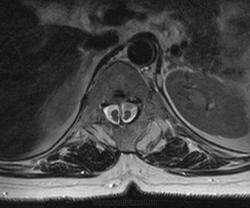

Диастематомиемия.

Диастематомиемия -

Диастематомиемия (Тип 1)

Диастематомиемия (Тип 2)